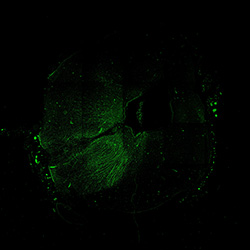

An anatomical analysis of the developing human midbrain from 6 post-conceptional weeks (PCW) to 22 PCW reveals increased tissue complexity, characterized by the emergence of dopaminergic nuclei, as highlighted by immunofluorescence analysis for tyrosine hydroxylase (TH).

7PCW

TH

7PCW human midbrain

Merged